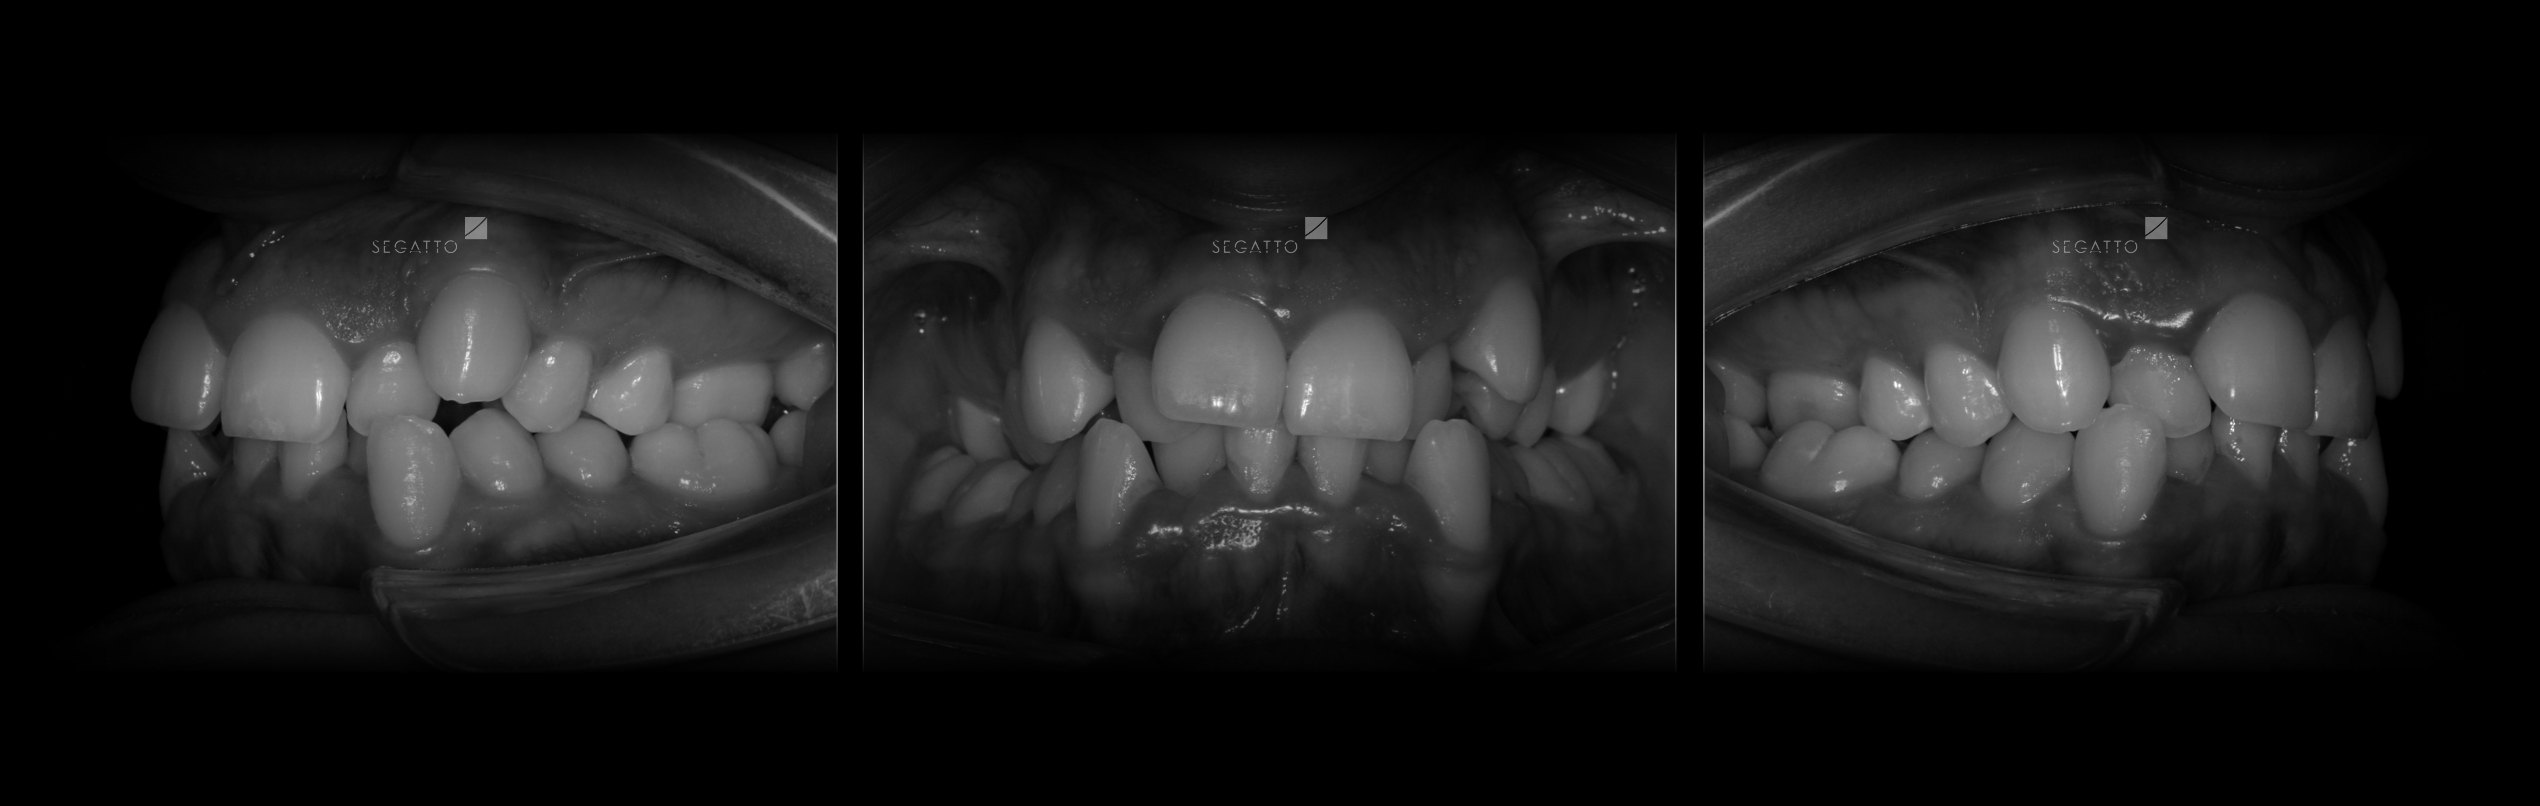

Orthodontics

Cases